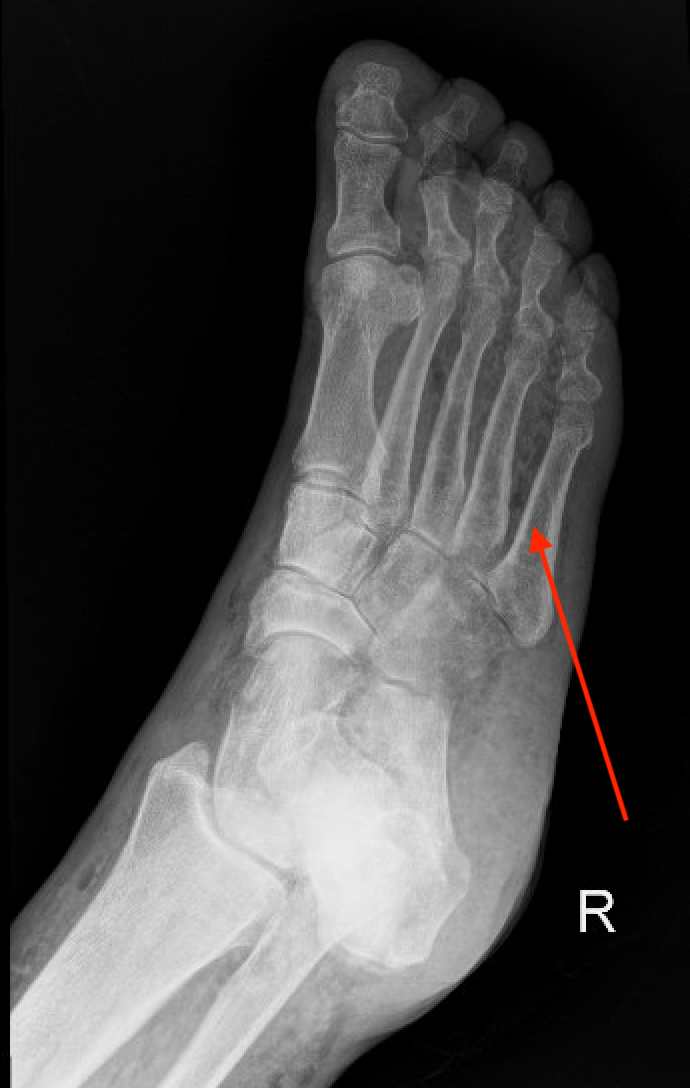

Necrotizing Fasciitis

Most often patients have a history of pain and swelling over the course of hours to days.

Physical exam findings may include hemorrhagic bullae, skin necrosis, crepitus, cutaneous sensory deficit and firm woody edema. Keep in mind that these findings are not always present and a high clinical suspicion should prompt further investigation. The pain and extent of the infection may be out of proportion to the external appearance.